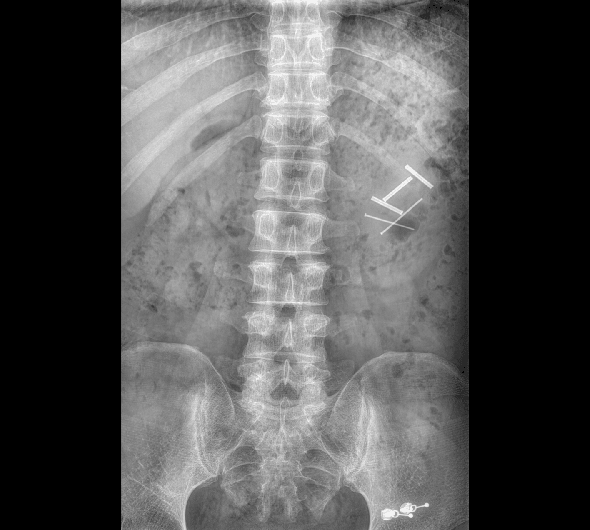

臨床圖像